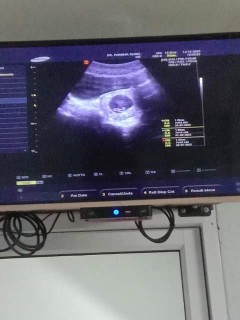

อันนี้คือรูปซาวตอน9วีค3วันหมอบอกว่ายังไม่เจอตัวเจอเเค่ถุงไข่เเดง อยากทราบว่าเเม่ๆซาวเจอตัวน้องตอนกี่วีคคะ